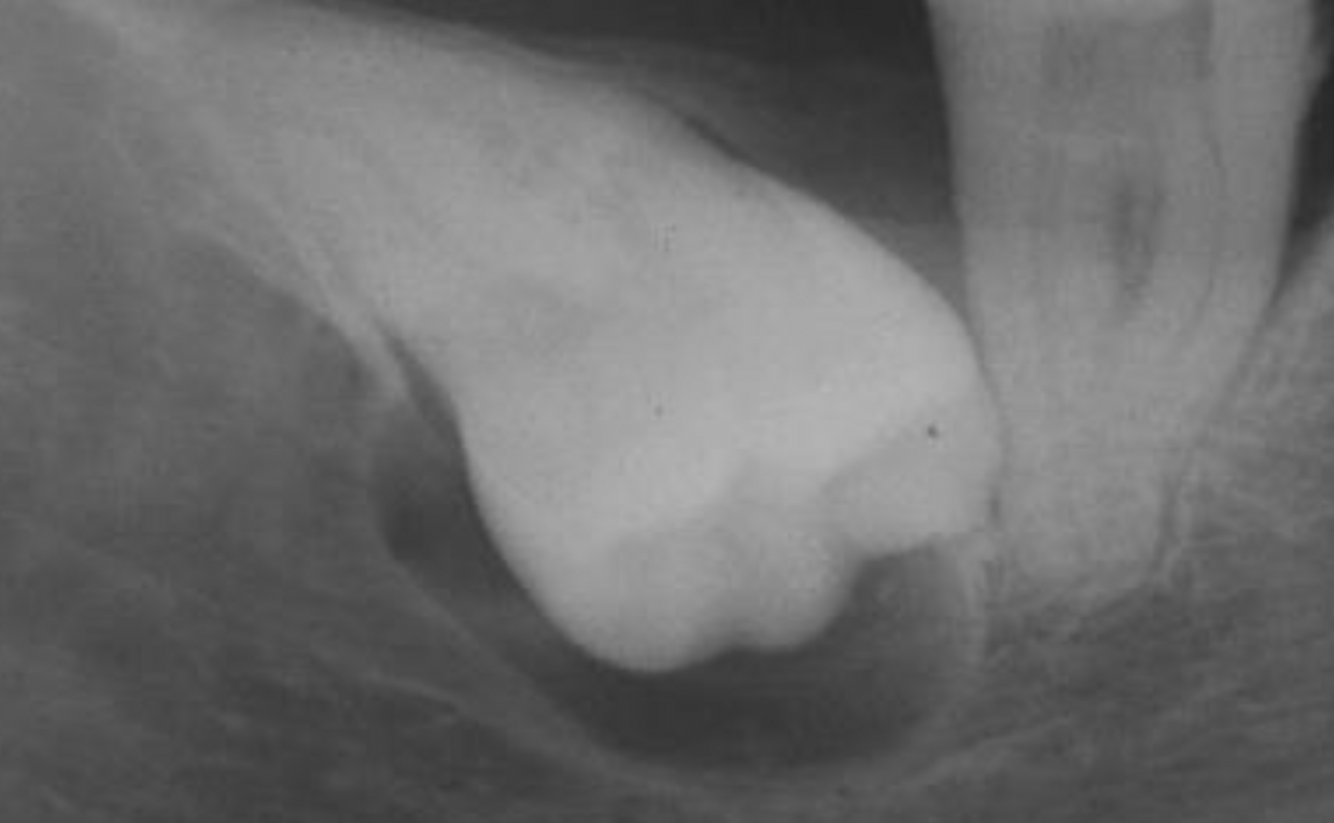

7

A

dentigerous cyst